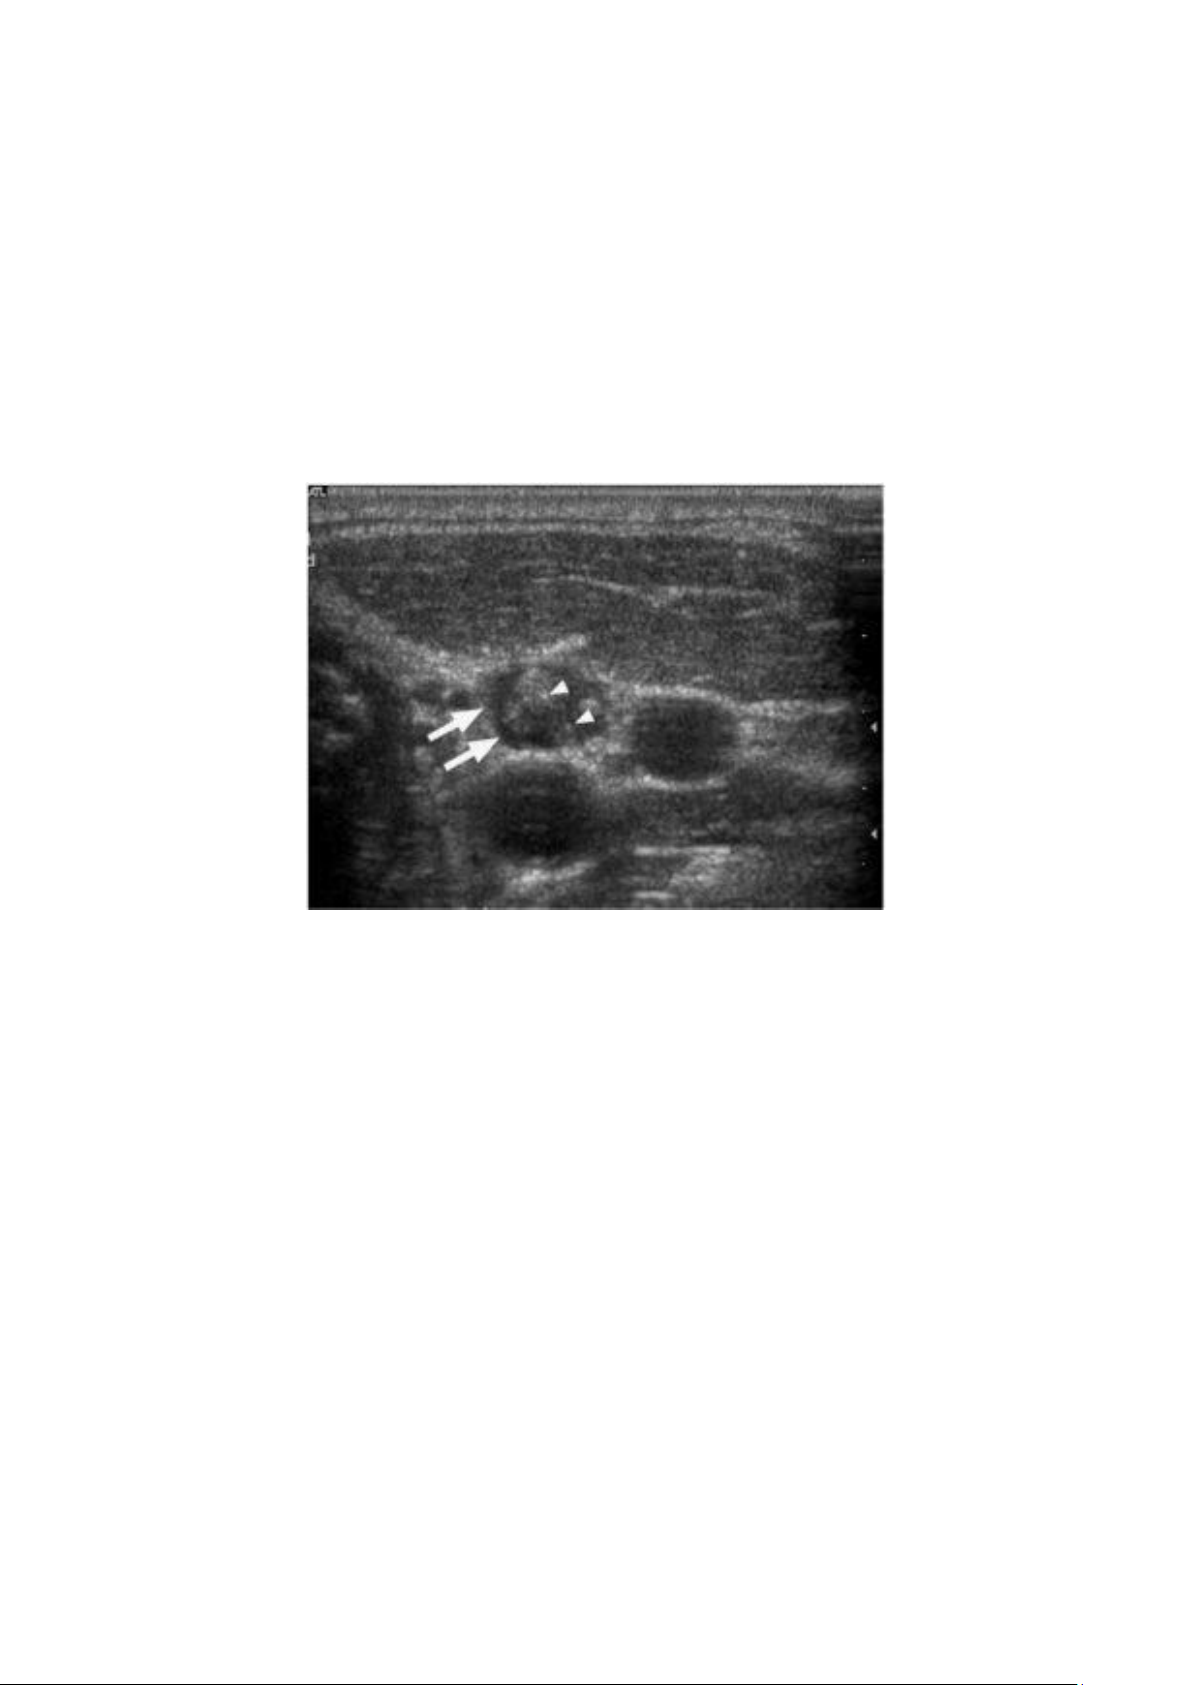

Hình 1.1. Siêu âm trắng đen cho thấy hạch di căn tăng kích thước, hồi âm kém, đường bờ rõ

nét và mất rốn hạch (mũi tên)

Hình 1.2. Siêu âm trắng đen cho thấy hạch di căn từ ung thư biểu mô nhú tuyến giáp (mũi

tên). Lưu ý thành phần hồi âm dày trong hạch có thể liên quan đến sự lắng đọng

thyroglobulin (đầu mũi tên).